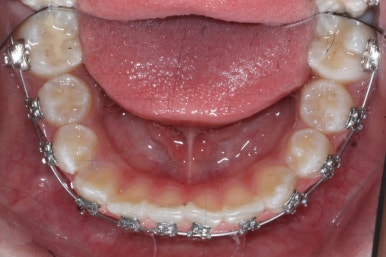

영구치도 이제 거의 다 나왔고 삐뚤한 다른 부분도 전체 메탈장치를 붙였습니다.

장치는 윗니부터 붙였습니다.

입안에 장치가 있다보니 불편할 수 있는데요. 이물감을 최소화 하고자 이동을 해야 할 양이 적은 아랫니들은 천천히 장치를 붙이기로 했습니다.

아래쪽에도 이제 장치를 전부 부착했습니다.

한 쪽의 송곳니는 제위치로 벌써 자리를 잡았네요.

장치를 부착한 후에 순차적으로 변화가 나타나는 모습입니다.

총 4장의 사진 동안 경과한 시간은 불과 6개월 입니다. 헤드기어를 통해 사전에 작업을 해뒀기 때문에 이후 연산동덧니교정 과정은 편해진 것이죠.

윗니만 6개월이 지난 모습입니다.

치열이 매우 가지런해졌죠. 이 후에는 특이사항 없이 종료가 되었습니다.